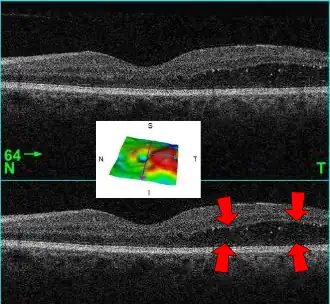

El diagnóstico debe realizarlo el oftalmólogo, que puede distinguir el engrosamiento de la mácula mediante técnicas especializadas; también puede sospecharse mediante la exploración con oftalmoscopio en la que se aprecia una zona de exudados amarillentos que rodean a la mácula, asemejándose a una corona (ver imagen).